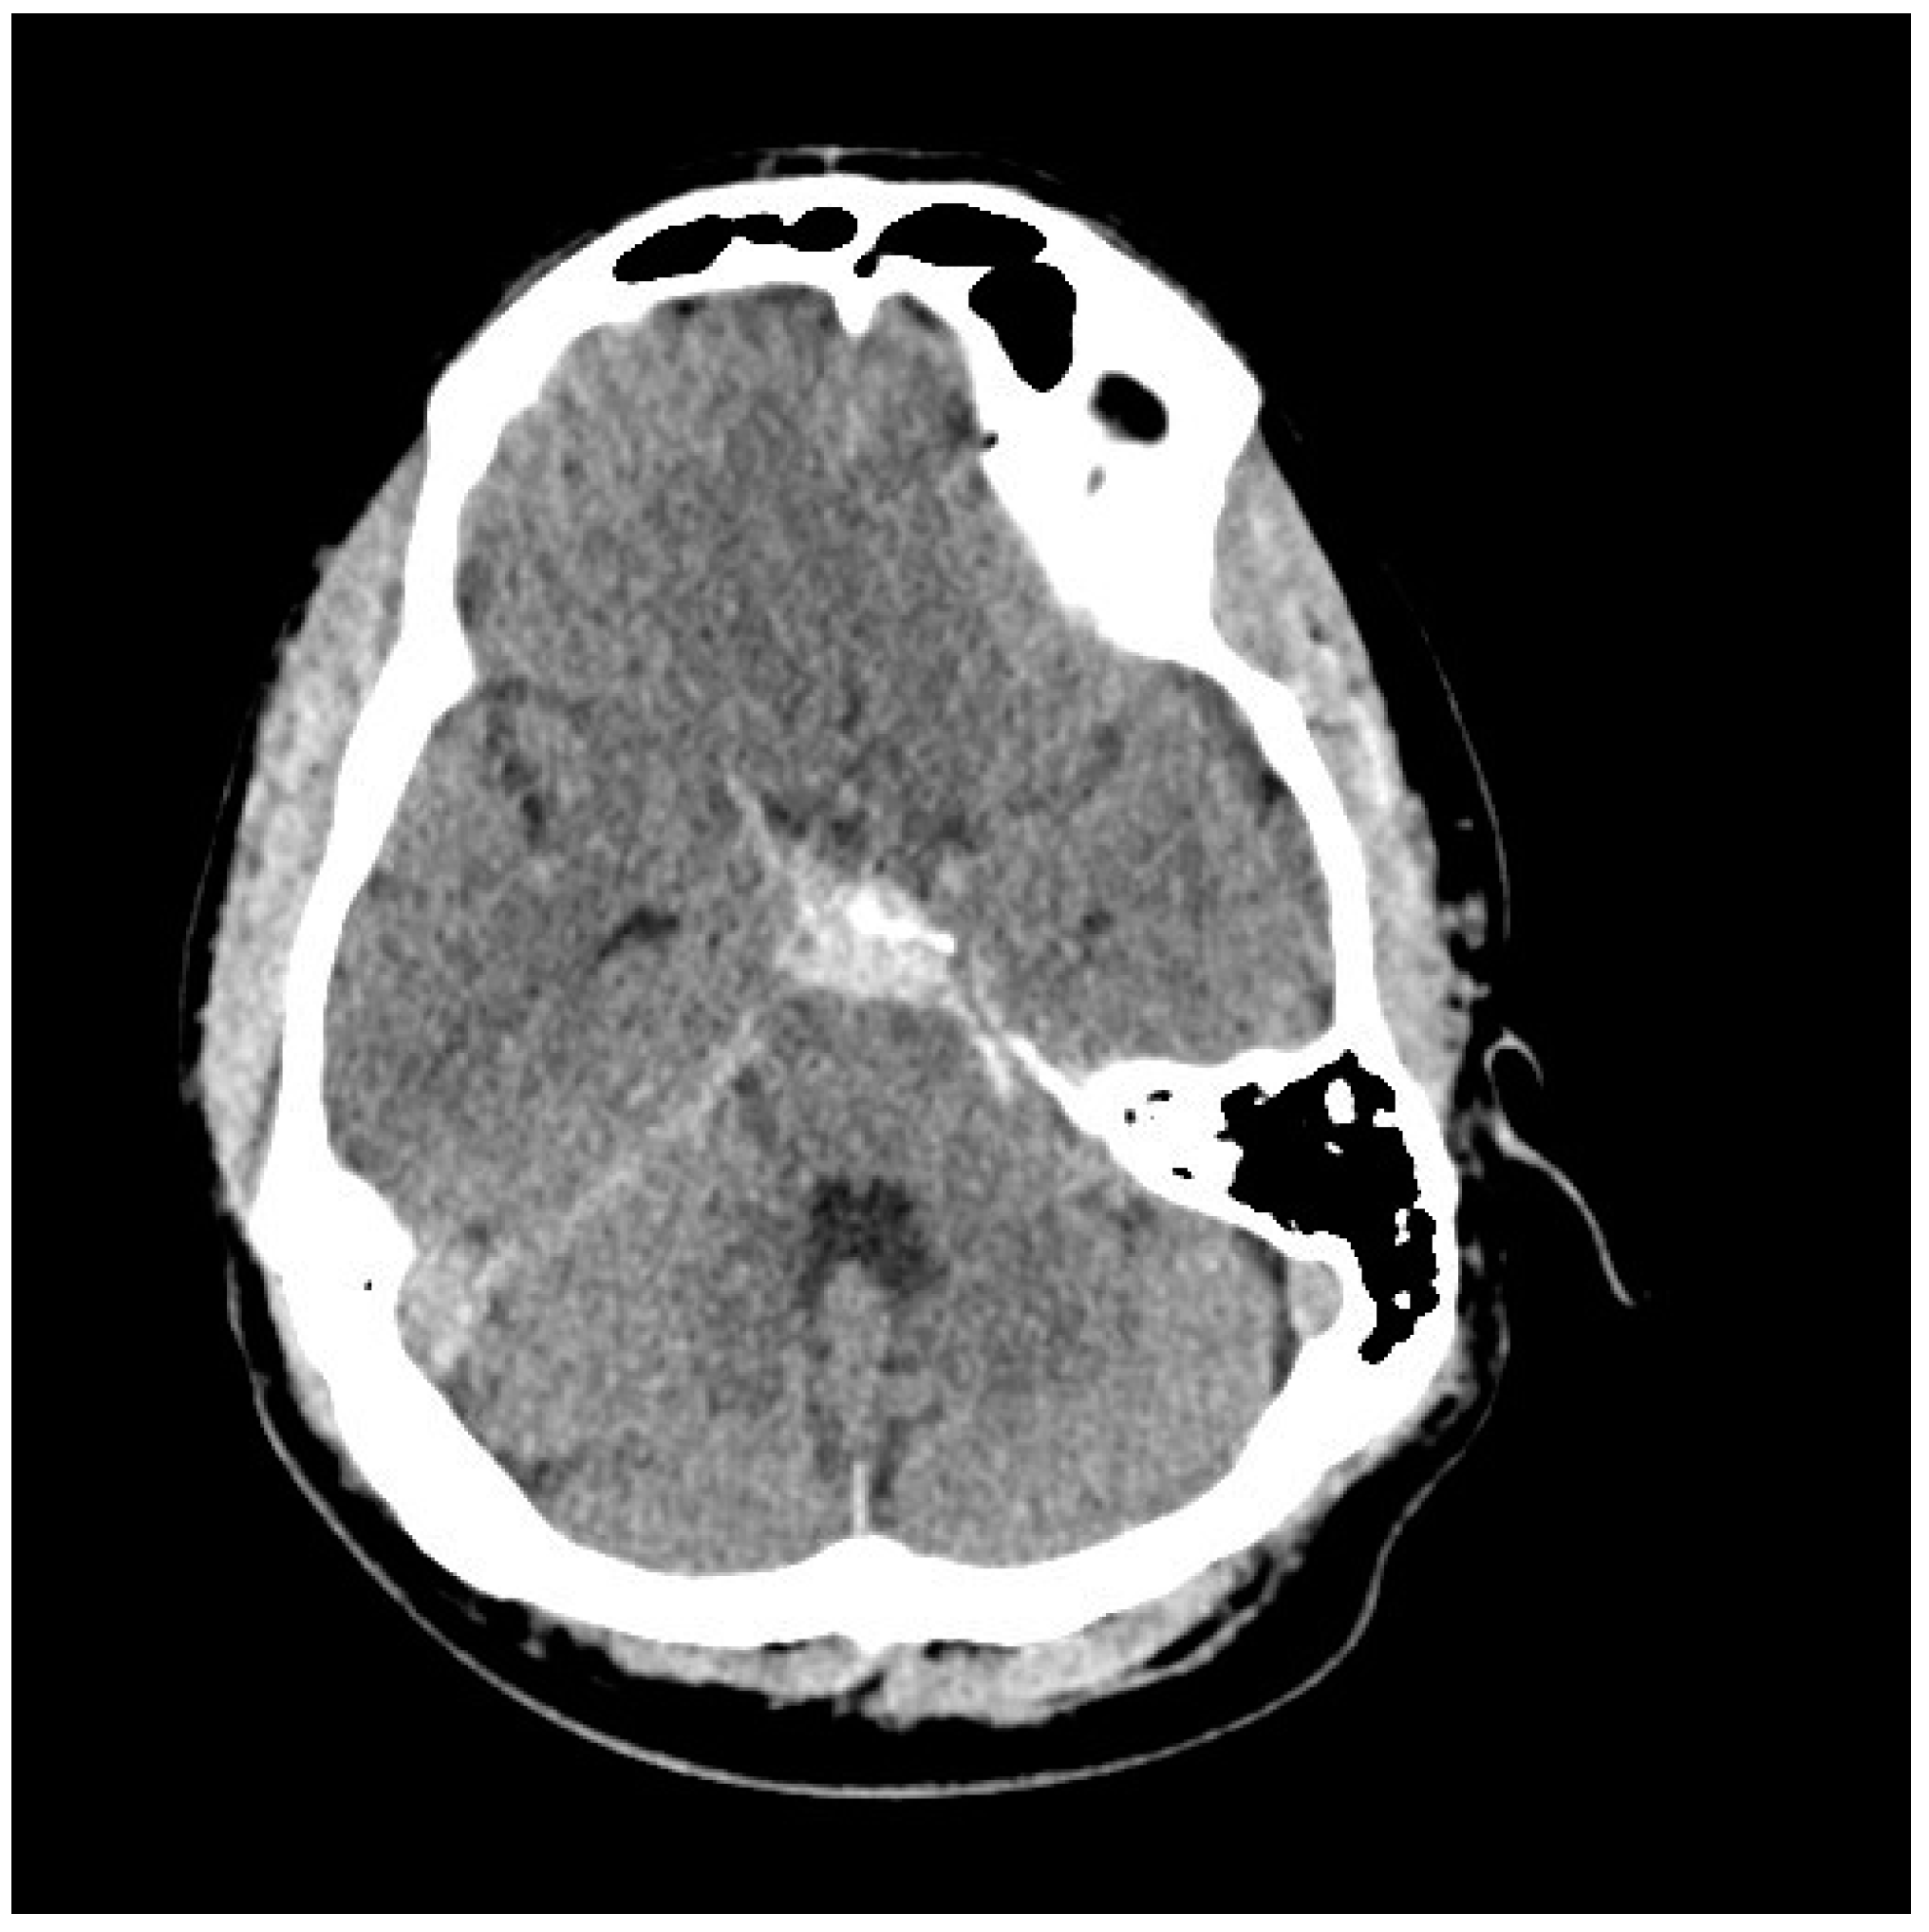

5. Diagnosis